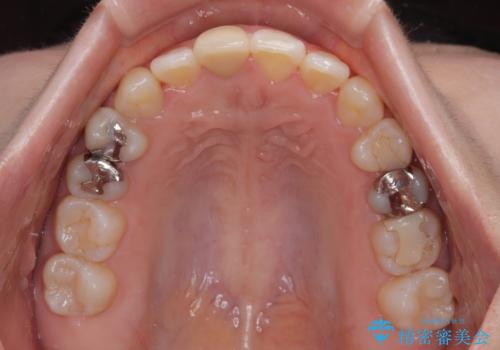

- 学生時代に行った抜歯矯正の後戻りで、隙間ができてしまったことを気にして来院された患者様です。

マウスピース矯正を検討されていましたが、後戻りの隙間が非常に大きく、奥歯を前方に移動させる必要があるため、ワイヤー装置にて矯正治療を行うこととしました。

上顎歯列は歯の移動量が少なかったため、セラミッククラウンは装置を装着せずに治療を終えることができました。